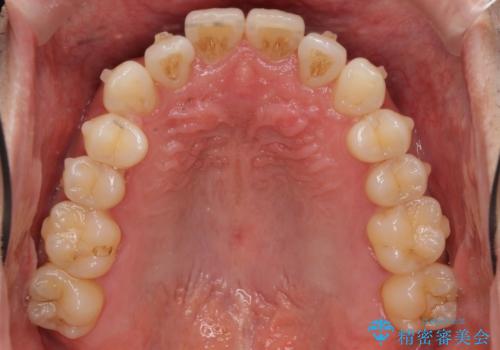

受け口 マウスピースで矯正治療 難易度:中

- 受け口を主訴に来院。

前歯の反対咬合でしたが、かみ合わせが、下顎が大きく前方にずれていました。

引っ込んでいる前歯の前方に下の犬歯が深く咬み込んでおり、また、奥歯のかみ合わせも受け口方向にずれ、骨格性の反対咬合も少々ありました。

上の前歯を前方に出すだけでは治療ができないため、ミニスクリューを用いて下の奥歯を後ろに送っています。

また、下の前歯を0.3mmずつIPRしています。

前歯の反対咬合にしては、難易度は中等度だと思います。

ちょっと前歯を外に出すだけでは治療は難しいです。

下の奥歯を後ろに送るにも、親知らずを抜いたスペース等がなければ難しいです。